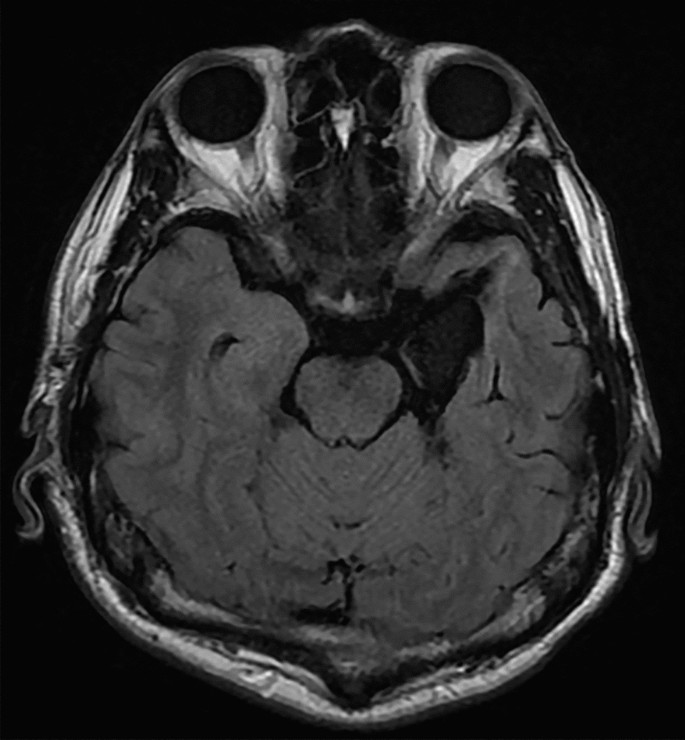

To test this hypothesis, we evaluated 16 patients with unilateral temporal lobe resections, inclusive of the amygdala (Fig. 1 and Supplementary Fig. 1), utilizing a subliminal affective priming paradigm41 combined with unilateral visual presentation (Fig. 2). Dynamic fearful and happy facial expressions were presented briefly for 30 ms42 as negative and positive primes, followed by a mosaic mask, then neutral faces as target stimuli. Then the participants rated the emotional valence of these neutral target faces. Prior research suggests that in the affective priming paradigm, participants’ emotional assessment of the target is shifted toward the positive by unconscious positive primes, in contrast to negative primes41,43. This phenomenon is taken as evidence that emotions are unconsciously elicited and subsequently influence target evaluations41. This subliminal affective priming approach provides insights into the valence of unconscious emotion. We chose to present dynamic facial expressions because a previous study showed that dynamic expressions were more effective in inducing unconscious emotional responses than static expressions in a subliminal affective priming task42. We integrated this paradigm with unilateral visual field presentation. Given that visual stimuli presented to one visual field are predominantly processed in the opposing hemisphere44, we contrasted the valence ratings between the intact and resected hemisphere stimulation conditions as in previous studies28,40,45. We predicted that when primes stimulated the intact hemisphere (i.e., presented to the visual field opposite the intact hemisphere) compared to when they stimulated the resected hemisphere (i.e., presented to the visual field opposite the resected hemisphere), the distinction between positive and negative prime effects would diminish. To investigate conscious emotional processing, we also exploratorily presented dynamic facial expressions supraliminally (lasting 200 ms) and prompted participants to evaluate the valence of these expressions.

Sixteen patients (10 females, 6 males; mean ± SD age = 34.8 ± 12.4 years) with unilateral resection of medial temporal lobe structures due to pharmacologically intractable seizures participated in the study. We conducted a priori power analysis using G*Power 3.1.9.2 software68 to determine the necessary sample size, assuming that a paired t-test (one-tailed) would be used to compare the intact and resected hemisphere stimulation with an α level of 0.05 and a power of 0.80. Because the effect size was unclear, we assumed a medium-sized effect (r = 0.36). The results indicated a requirement of 12 participants. All participants had undergone surgery at least 1 year before the experiment. For most participants, seizures were effectively managed (n = 13, 2, and 1 for Engel classes69 I [free from disabling seizures], II [rare disabling seizures], and IV [no worthwhile improvement], respectively), and they were mentally stable during the experiment. The resection methods included selective amygdalohippocampectomy, involving the amygdala, anterior hippocampus, and parahippocampal gyrus in seven individuals; and anterior temporal lobectomy, involving the amygdala, anterior hippocampus, anterior lateral temporal neocortex (from the temporal pole to 4–5 cm), and parahippocampal gyrus in nine individuals. Postoperative magnetic resonance imaging validated the targeted resections in all patients (Fig. 1). Among the 16 participants, 8 (3 females, 5 males; mean ± SD age = 32.4 ± 13.4 years) and 8 (7 females, 1 male; mean ± SD age = 37.1 ± 11.7 years) had undergone resection of the left and right hemispheres, respectively. We assessed handedness using the Edinburgh Handedness Inventory70, confirming that all participants were right-handed. All had normal or corrected-to-normal vision and provided written informed consent after receiving a detailed explanation of the procedure. The Ethics Committee of Shizuoka Institute of Epilepsy and Neurological Disorders approved this study. The experiment was conducted in accordance with institutional ethical guidelines and the Declaration of Helsinki.